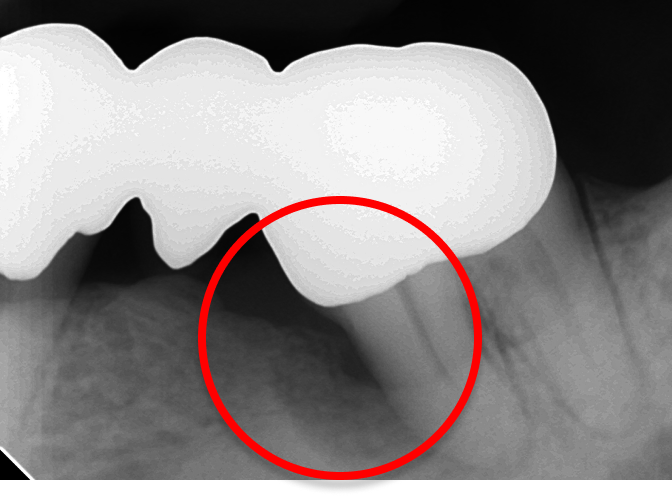

※丸印内の歯周骨が

吸収されました。